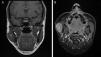

Acta Otorrinolaringológica Española Tumor de células granulares en músculo masetero

Tumor de células granulares en músculo masetero

Granular cell tumour in the masseter muscle